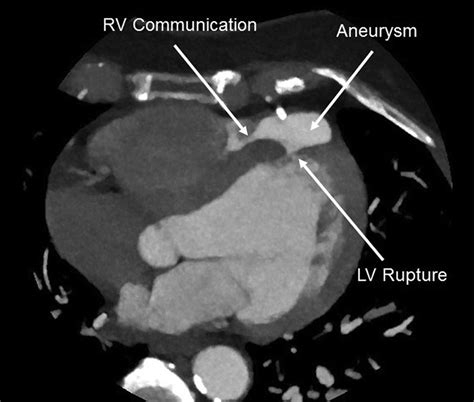

• Rupture: In severe cases, the aneurysm can rupture, leading to sudden death.

• left ventricular free wall rupture

• left ventricular aneurysm vs pseudoaneurysm